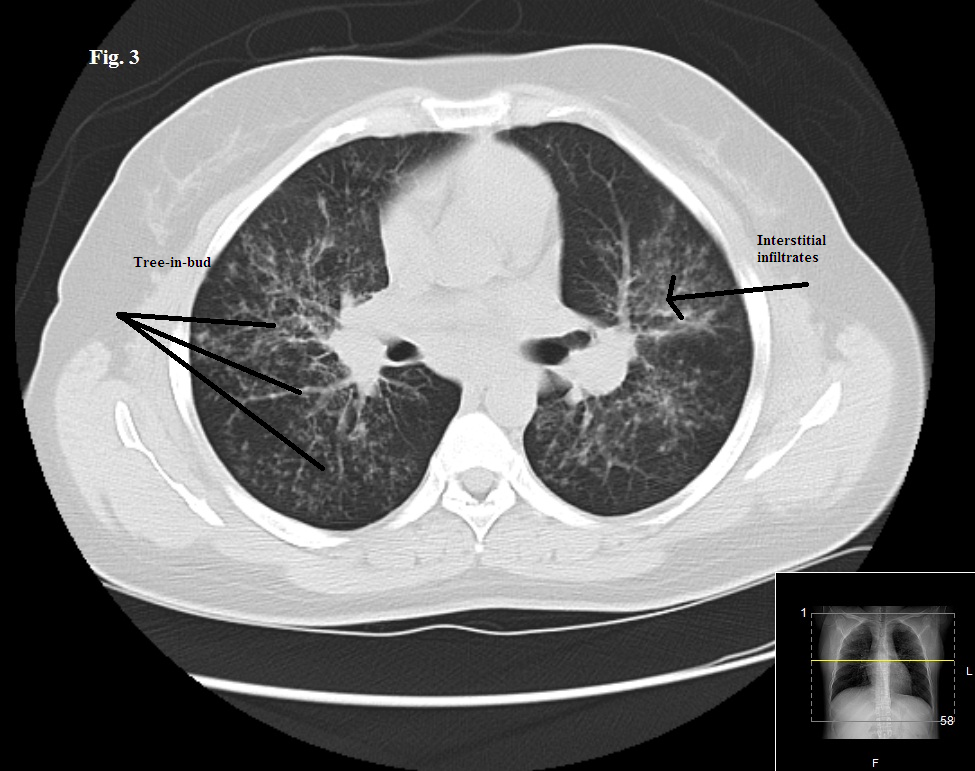

A 44-year-old African American woman was evaluated for symptoms of worsening cough, shortness of breath, chest tightness, and fatigue of 6 months’ duration. Bronchial asthma had been her diagnosis 2 years earlier, and she had been compliant with her inhalation therapy.

The physical exam showed bilateral diffuse wheezing and crackles. An earlier chest radiograph showed mild hilar prominence. A repeated radiograph showed new bilateral diffuse interstitial infiltrates involving both lungs and bilateral hilar lymphadenopathy. This chest CT scan showed similar findings with a tree-in-bud appearance predominantly in the midlung zones and perihilar areas. Pulmonary function testing results showed a progression from moderate to severe obstructive lung disease and worsening diffusing capacity of the lung for carbon monoxide.

Positive findings of sarcoidosis involving the skin along with bilateral diffuse interstitial lung infiltrates and hilar lymphadenopathy supported a diagnosis of pulmonary sarcoidosis.

Sarcoidosis affects the lungs in 90% of cases. It usually involves the intrathoracic lymph nodes and, less frequently, the lung parenchyma. Up to 50% of patients have symptoms similar to those of asthma, such as cough, wheezing, dyspnea, chest pain, chest tightness, and fatigue.